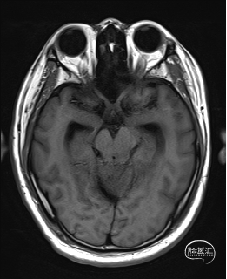

术前MRI检查

术前MRI检查提示左侧丘脑中脑海绵状血管瘤并卒中,梗阻性脑积水;

诊断:1.左侧丘脑中脑海绵状血管瘤并卒中,2.梗阻性脑积水;

根据MRI及DTI显示,只有在丘脑与上丘之间的点(dot)进入病变才可能在切除病变时最大程度保护神经功能,由于上述原因,该“点”在术中显露极其困难,虽有导航指引,电生理监测的条件下,对术者的耐心、技术、经验及体能依然是极大的挑战;

本例患者磁共振检查清晰显示病变位于左侧丘脑中脑区域,且位于丘脑内下方向中脑顶盖延续,病变的上部、前部、外侧部都有重要的神经组织,因此,手术从上方、前方、外侧方向切除病变均难以实施;

从后方有POPPEN入路、Krause入路等,但是因为病变并未充分向松果体区、大脑大静脉后方突出,有大脑大静脉复合体的阻挡,POPPEN入路有较大的难度显露及切除病变,残留的可能性比较大;传统显微镜下进行的幕下小脑上入路在病变的显露及切除上依然有较大的难度。